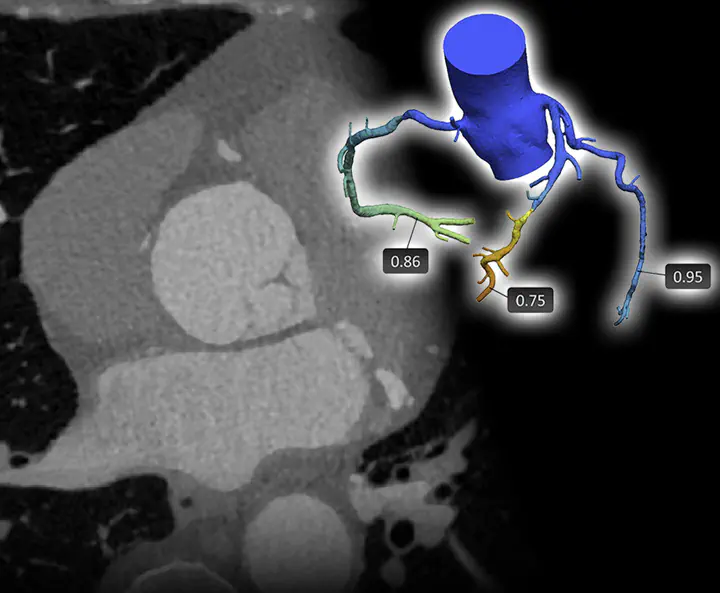

Case D: Non-invasive Identification of Patients Requiring Invasive Coronary Artery Treatment

Background: Invasive methods for diagnosing coronary artery disease through catheterization, such as invasive coronary angiography (ICA) and fractional flow reserve (FFR), are considered the gold standard for measuring the severity of stenosis in patients with coronary artery disease. Coronary CT angiography (CCTA) is a non-invasive imaging technique that enables the detection of both stenosis and plaque in the coronary vessels. Thanks to its high sensitivity, it is used as a first-line diagnostic tool for identifying which patients require catheterization for further invasive treatment. Nevertheless, studies have shown that 20 to 50% of patients identified using CCTA did not, in fact, have significant functional stenosis. In view of this, numerous AI image analysis models have been proposed that combine CCTA with functional stenosis measurements through computed tomography-derived FFR (CT-FFR), to increase specificity and thus reduce unnecessary admissions to the cath lab. Despite their success, they are prone to errors when presented with suboptimal image quality and heterogeneity in the image data.

Objective: The goal of this work is to extend the applicability of AI-based analysis to this use case by developing methods robust to artifacts and outliers. This will facilitate the accurate identification of patients requiring invasive treatment, thus making diagnosis more accessible to patients in hospitals with less advanced imaging equipment. Finally, to enable autonomous employment of our proposed methods, special attention will be paid to ensuring their interpretability by clinicians and medical staff.